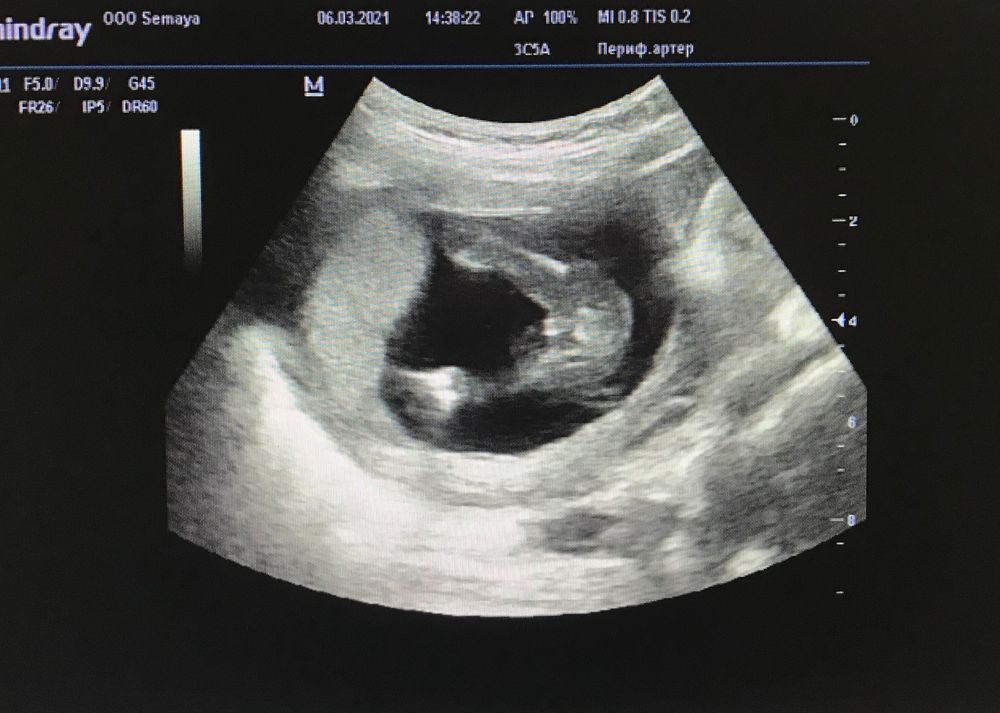

Вот писюн в 19 недель . Прям очевидный, с головкой

НЮША (ник в ИГ Visla79), мне показалось, что фото с моего узи похоже на ваше. Вы уж меня извините, я сделала коллаж с вашим фото. Просто я повернутая мамаша. Вам не кажется, что похожи? Вы мама с хорошим опытом)

Оксана, честно на впшем фото плохо видно, я бы сказала больше на девочку похоже

Ой, вы и комментаторы мне сейчас дали надежду. У нас фото 15 недель один в один. Но врач сказала, что якобы видит там мошонку и пенис. При этом ничего спереди не торчит, как и у вас.

Смотрела снимки с беременности сыном. В 18 недель там прям четко были мужские половые органы. Но я все равно волновалась, вдруг просто оно за 3 недели отрастет, и в этот раз у нас тоже мальчик.

Конечно девочка ! У меня фото парня с 16 недель- там прям пипирка торчит